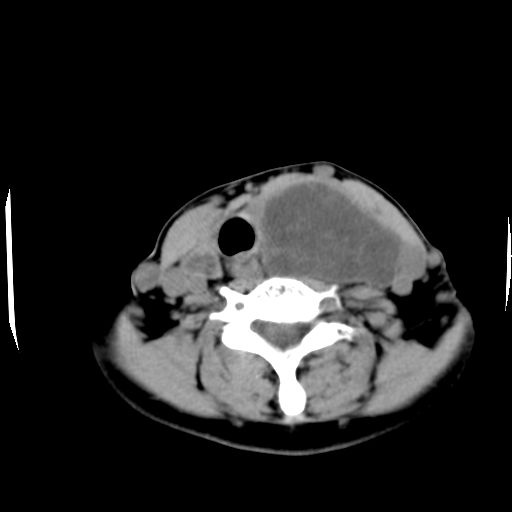

女  53岁  左侧甲状腺肿物3年,近2月明显增大。病理稍后发。

左侧甲状腺内见有一较大类圆形低密度区,边缘清楚光整,增强有一定强化,但仍较正常甲状腺组织强化弱,左侧甲状腺周围组织明显受压移位,且周围组织界限存在,周围组织间隙内未见肿大淋巴结,结合病史考虑为良性病变,左侧甲状腺腺瘤可能大。

左侧甲状腺内见有一较大类圆形低密度区,边缘清楚光整,增强有一定强化,但仍较正常甲状腺组织强化弱,左侧甲状腺周围组织明显受压移位,且周围组织界限存在,周围组织间隙内未见肿大淋巴结。

考虑:甲状腺囊腺瘤

双侧都有,最大病灶在左侧,其包膜和灶内部都有明显的强化,提示其血供丰富。我首先考虑是良性占位,以腺瘤可能性大。

左侧甲状腺内见有一类圆形低密度区,边缘清楚光整,可见明显增强,间隔亦可见增强,且与周围组织分解清晰,周围组织间隙内未见肿大淋巴结。右侧亦可见类似表现。考虑甲状腺腺瘤。

手术病理证实:双侧腺瘤样甲状腺肿。